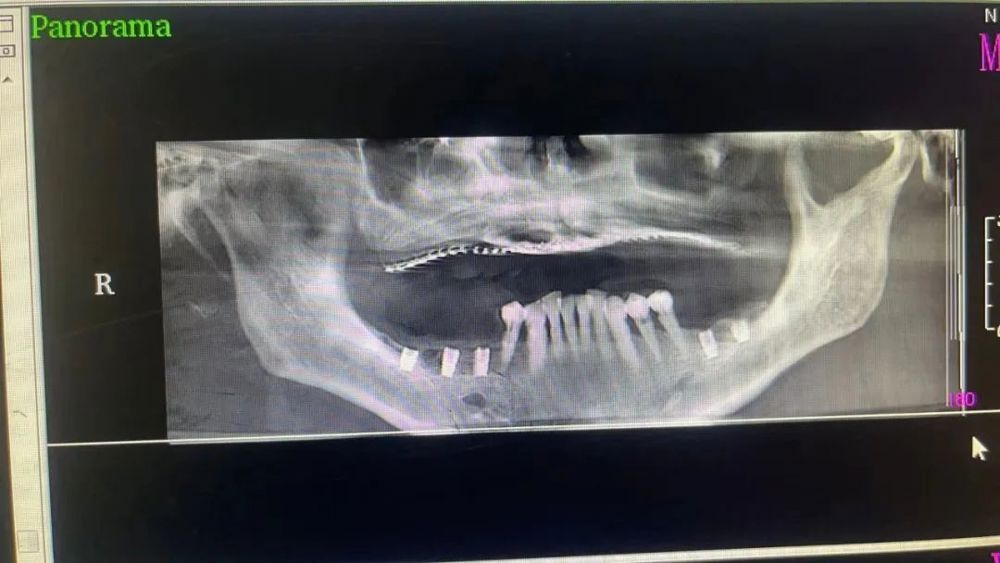

三、種植牙技術

目(mù)前,社會上很多(duō)人被牙齒缺失所(suǒ)困擾,牙齒缺失不但影響人的咀嚼和(hé)語言功能,對於人的(de)麵(miàn)部(bù)美觀也是一種影響,甚至有些人因(yīn)缺失牙齒而(ér)不願意張口說話,種植牙被譽為(wéi)人類“第(dì)三(sān)副牙齒”,因其舒適(shì)、美觀(guān)、功能(néng)好而被缺牙患者追捧。經衛生(shēng)健康委批準,我院於2023年(nián)3月18日正式(shì)開展種植(zhí)牙技術,開(kāi)展當天門診手術7例共計14顆植體,術(shù)後1天回訪患者表示無紅腫、無疼痛症狀(zhuàng),術後(hòu)7天回訪(fǎng)一切良好無異常,術後10天拆線創口愈合良好,自開展口(kǒu)腔種植手術以來,有許多患者紛紛到科裏(lǐ)進行相關谘詢和(hé)檢查,更是不斷有患(huàn)者預約意向種植,我院嚴格按照江(jiāng)西省醫療保障局、江西省衛生健康委員(yuán)會(huì)關於(yú)公布實施口腔種植類醫療服務價格有關事項的通知—贛醫保字《2023》3號文(wén)件執行操作,在手術診療中,嚴(yán)格操作流程,減少感染風險。我院(yuàn)口腔種植技術的成功和發展,不僅完善了傳(chuán)統牙齒修複(fù)技術的不(bú)足,而且在功能與(yǔ)美觀上給了(le)人們嶄新的體驗,我院致力於提供一站式口腔種植診療服務,必將為(wéi)本縣及周邊缺(quē)失牙患者找回美麗、自信的微笑。

案例(lì)一

種植前與種植後

案例二

種植前與種植(zhí)後